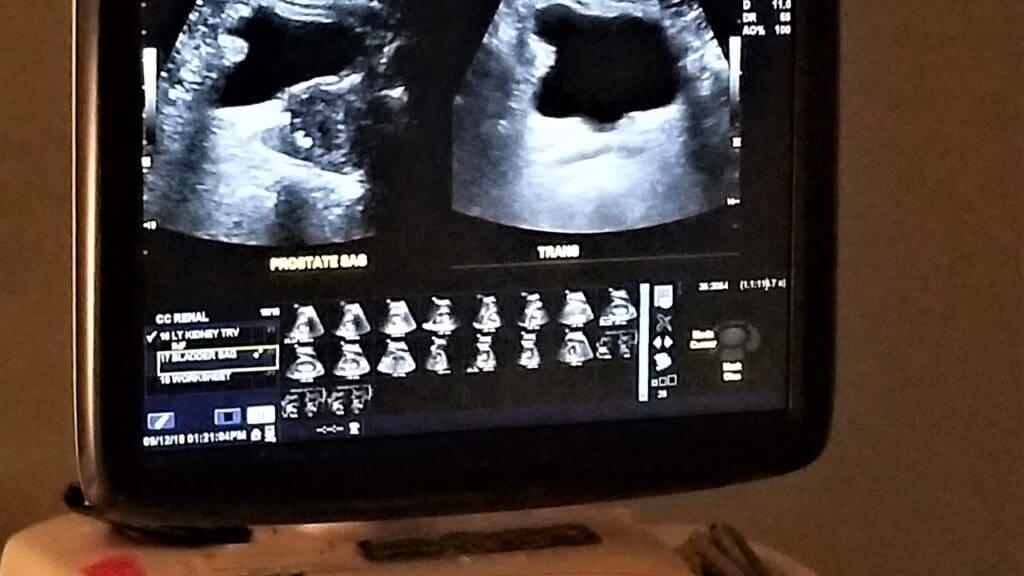

Key Fact #1: How Ultrasound Detects Aortic Weakening

Ultrasound is key in triple AAA screening. It uses sound waves to show detailed images of the aorta. Doctors can then measure the aorta’s size and spot any problems.

Studies show ultrasound is very good at finding AAAs, with over 95% accuracy.

Non-Invasive Nature of the Procedure

Triple AAA screening is non-invasive. It doesn’t need cuts or instruments inside the body. This makes it safe and easy for patients.